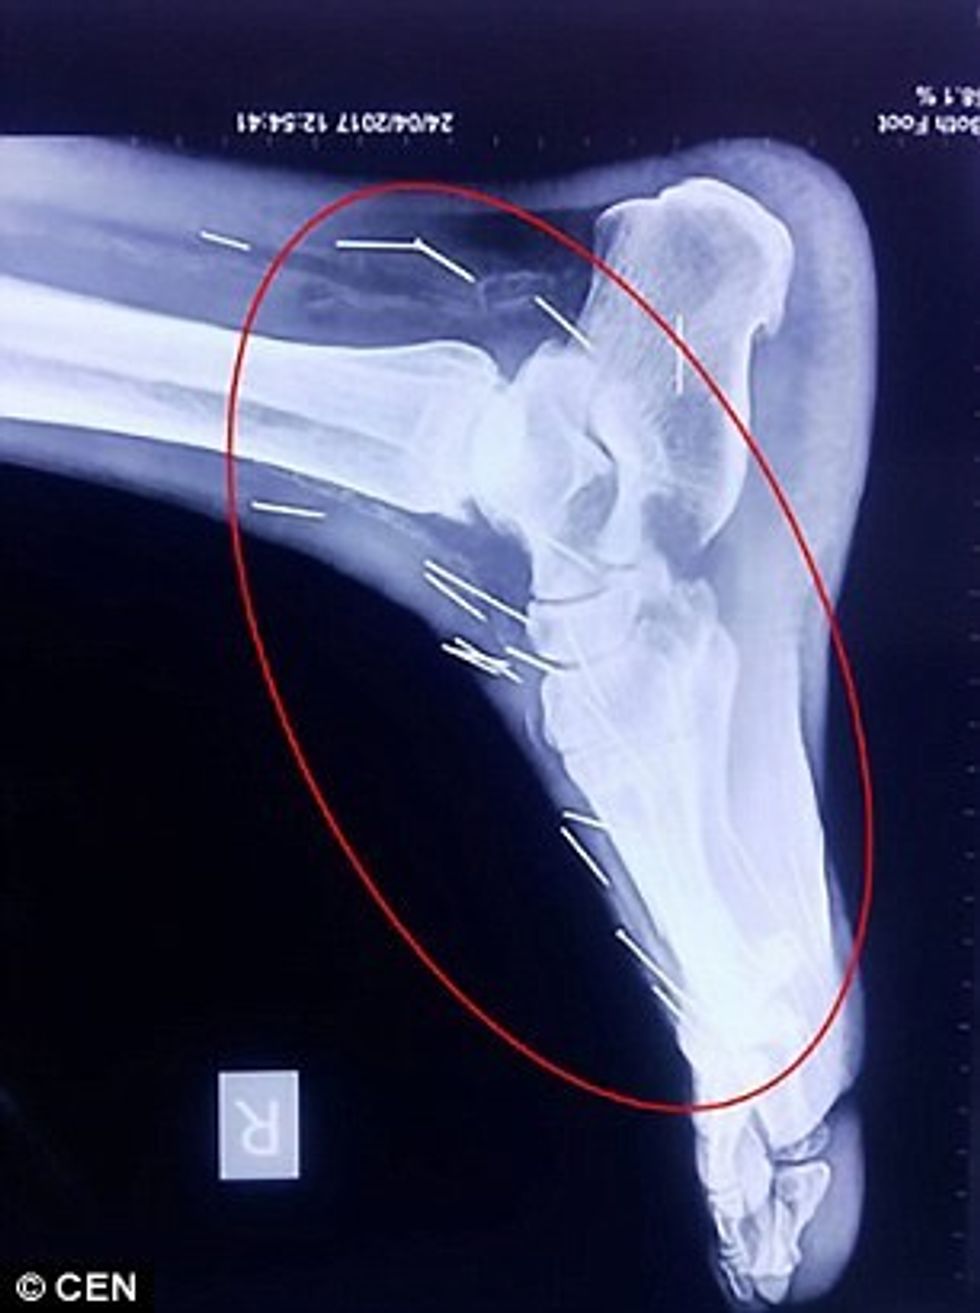

Badrilal Meena nga Kota i Indisë, kishte shkuar te mjeku me dhimbje të mëdha në gishtin e madh të këmbës, por është befasuar kur i janë gjetur 75 gjilpëra në pjesë të ndryshme të trupit.

Fillimisht, atij ia kanë zbuluar në shputën e këmbës, pastaj është vendosur t’i bëhet një fotografim komplet me rreze X, mirëpo nuk është zbuluar prejardhja tyre.

Megjithëse është shtrirë në spital, ende nuk është intervenuar që t’i hiqen 40 gjilpëra nga fyti, 25 nga këmbët dhe dhjetë të tjera nga duart.